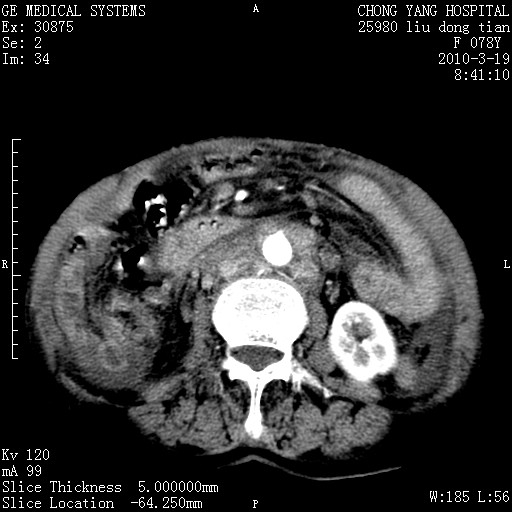

标题: CT25199:F 78Y 腹胀半年 消瘦乏力 [打印本页]

胆囊壁增厚并明显强化,胆囊癌伴多发转移瘤可能性大,淋巴瘤不除外,右肾囊肿,胸腹水.

考虑nhl,肝、脾、腹膜腔及腹膜后多发淋巴结受侵,腹水,右肾囊肿,慢性胆囊炎,右侧少量胸腔积液。

胰头有肿块形成,胰头ca伴肝脾、腹膜腹膜后转移

胆囊有软组织影有强化,支持胆囊癌,肝脾、腹膜后淋巴结转移。

nhl的淋巴结多围绕主动脉,而且主动脉会移位,所以不考虑nhl。

分开来讲:肝左叶、尾叶病灶有不均强化像肝癌;

脾脏病灶无强化,像多发囊肿或淋巴管瘤,不除外淋巴瘤(低强化);

胆囊增生性病变:胆囊癌,腺肌增生症,慢性胆囊炎;

肝门、胰腺头、腹膜后多个团块: 淋巴瘤,转移;

一元论最好了 淋巴瘤所致改变; 胆囊癌转移不像,胆囊周围肝组织清晰,肝癌淋巴结转移?三元论都不止。

脾脏病灶像车轮 莲花,第一感觉还像包虫呢。真想全切出来一个个做病检。

胰头ca伴肝脾、腹膜腹膜后转移!

最后报的胰头癌多发转移,脾脏单独考虑囊肿或淋巴管瘤。